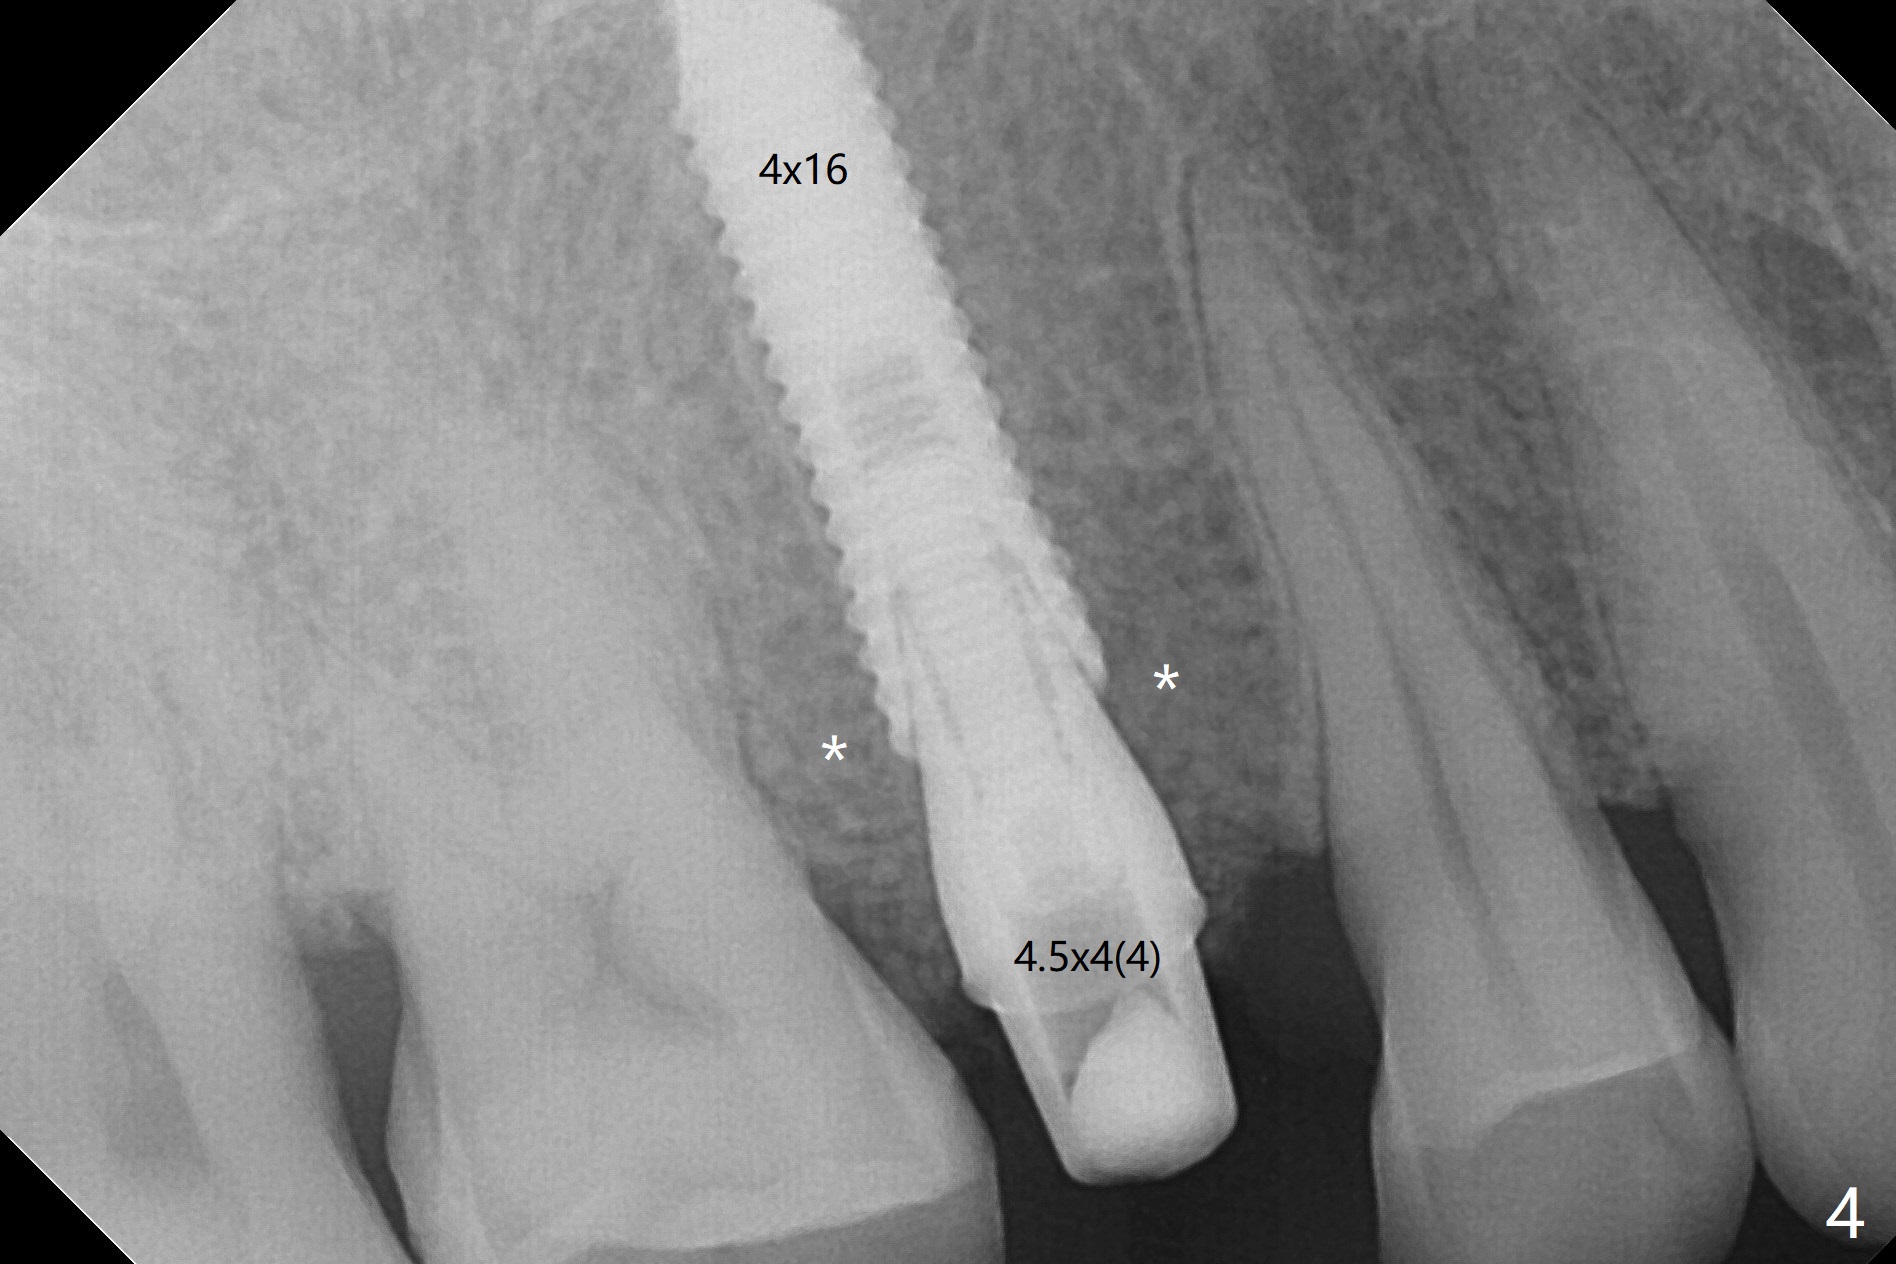

Why is 4x16 mm Placed Deep?

A 61-year-old man cracks the tooth #4 while chewing on a piece of chicken bone (Fig.1,2). Initial osteotomy appears to be able to hold a 16 mm long implant (Fig.3). After sequential osteotomy, a 4x16 mm implant is initially unable to be seated low enough for the buccal crest. Following packing the osteotomy with Vanilla Graft (.5-1 mm) and additional 2-3 mm depth of osteotomy, the implant is placed slightly apical to the buccal crest (Fig.4,5); with placement of Vanilla Graft (*) and a 4.5x4(4) mm abutment, an immediate provisional is fabricated to close the socket. The provisional is removed 3 months postop because of poor local oral hygiene (Fig.6,7). The gingiva is healthy 2-3 weeks later; it is easy to take impression (Fig.8).